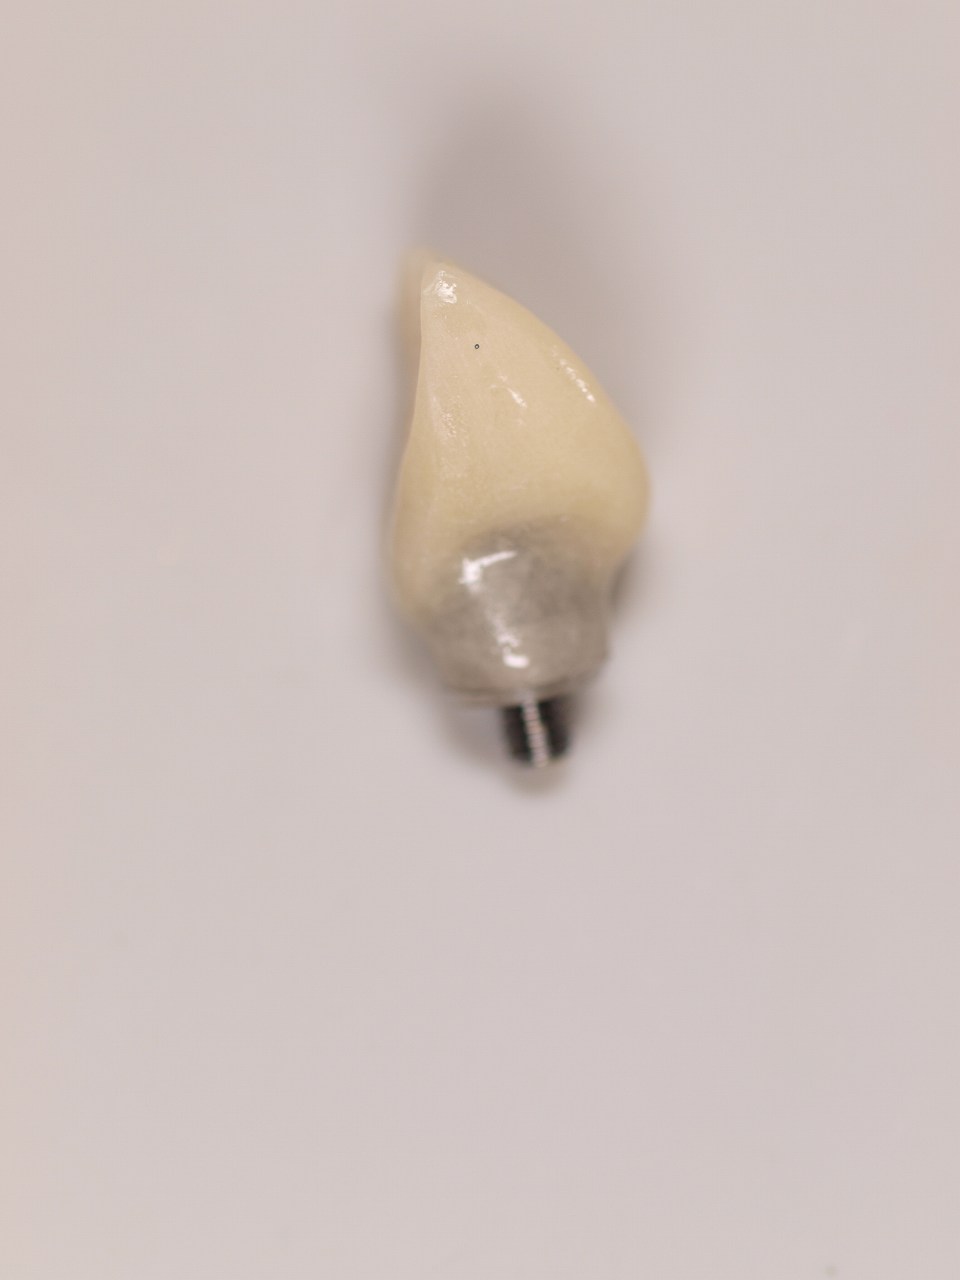

プロビジョナルを作成して装着し、歯肉形態を付与していきます

歯肉形態付与後になります